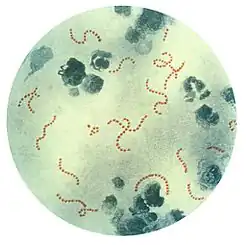

Rheumatic fever is a systemic disease affecting the connective tissue around arterioles, and can occur after an untreated strep throat infection, specifically due to group A streptococcus (GAS), Streptococcus pyogenes. The similarity between antigens of Streptococcus pyogenes and multiple cardiac proteins can cause a life-threatening type II hypersensitivity reaction.[12] Usually, self reactive B cells remain anergic in the periphery without T cell co-stimulation. During a streptococcal infection, mature antigen-presenting cells such as B cells present the bacterial antigen to CD4+T cells which differentiate into helper T2 cells. Helper T2 cells subsequently activate the B cells to become plasma cells and induce the production of antibodies against the cell wall of Streptococcus. However the antibodies may also react against the myocardium and joints,[13] producing the symptoms of rheumatic fever. S. pyogenes is a species of aerobic, cocci, gram-positive bacteria that are non-motile, non-spore forming, and forms chains and large colonies.[14]

S. pyogenes has a cell wall composed of branched polymers which sometimes contain M protein, a virulence factor that is highly antigenic. The antibodies which the immune system generates against the M protein may cross-react with heart muscle cell protein myosin,[15] heart muscle glycogen and smooth muscle cells of arteries, inducing cytokine release and tissue destruction. However, the only proven cross-reaction is with perivascular connective tissue. This inflammation occurs through direct attachment of complement and Fc receptor-mediated recruitment of neutrophils and macrophages. Characteristic Aschoff bodies, composed of swollen eosinophilic collagen surrounded by lymphocytes and macrophages, can be seen on light microscopy. The larger macrophages may become Anitschkow cells or Aschoff giant cells. Rheumatic valvular lesions may also involve a cell-mediated immunity reaction as these lesions predominantly contain T-helper cells and macrophages.[16]